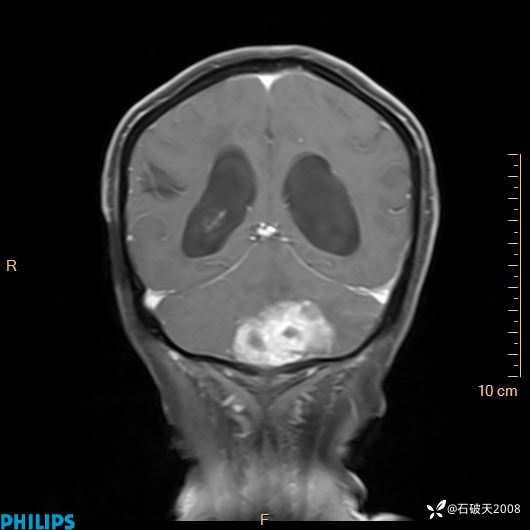

书上说这个肿瘤发生在幕下仅4.09%,你会想到它吗?(病理已公布)

女 86岁 主 诉:乏力1月

现病史:患者1月前活动出现双下肢乏力,无头晕、头痛、恶心、呕吐、肢体活动不利,休息后缓解,间断断发作,症状进行性加重,在家口服药物治疗(具体不详),效差,为进一步诊治,来我院,门诊按“乏力”收住我科,患者自发病以来,神志清,精神稍差,饮食睡眠欠佳,大小便正常,体重未见明显改变。

增强冠状位